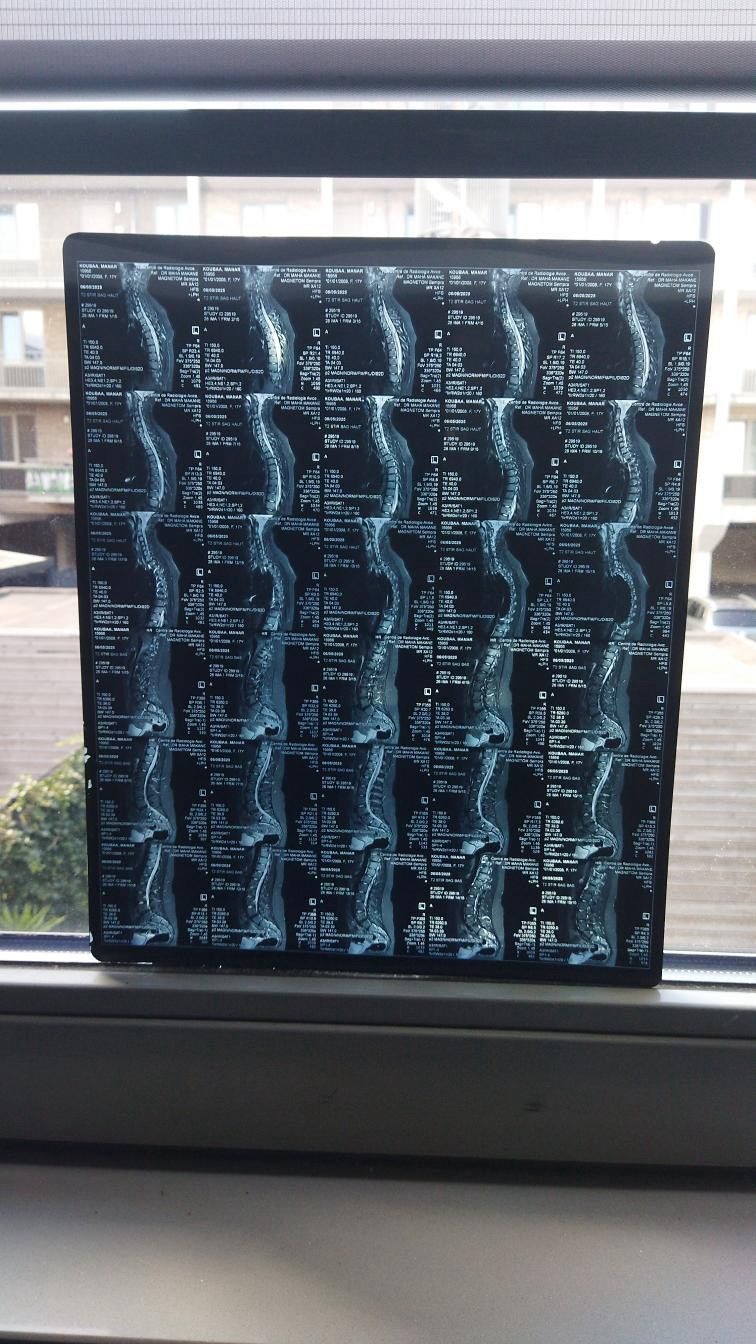

Ik ben Manar, ik ben 17 jaar oud. In mei 2025 heb ik de diagnose MS gekregen. Ik had veel last van duizeligheid, vermoeidheid en uiteindelijk dubbelzien. Uit verschillende onderzoeken is de diagnose MS vastgesteld. Iedere maand krijg ik via een infuus in het ziekenhuis medicatie toegediend, dit zorgt ervoor dat de ziekte geremd wordt. Helaas merk ik toch nog veel lichamelijke klachten waar ik dagelijks mee te maken heb. Dit beinvloed mijn dagelijks leven en het voortzetten van mijn studie. Al hamdoulilah 3la kouli hal.

Om te voorkomen dat mijn lichamelijke gezondheid niet verder achteruit gaat wil ik een stamcelbehandeling ondergaan in het buitenland. Een HSCT-behandeling, een intensieve behandeling waarbij het immuunsysteem wordt gereset. Deze behandeling kan de ziekte niet genezen, maar wel stopzetten en verdere verergering voorkomen. Deze behandeling kost € 65.000. Ik vertrouw er op met behulp van Allah en onze geweldige ummah dit bedrag te kunnen verzamelen, in sha allah.